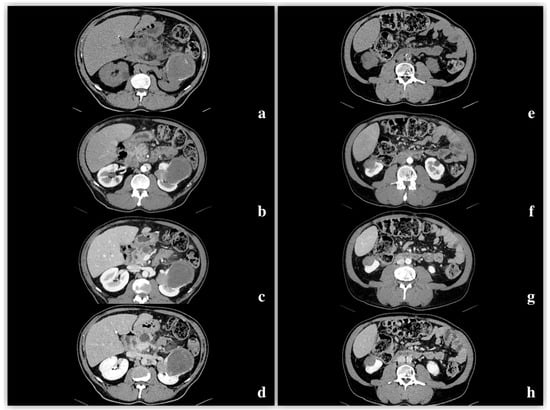

3.3. CT

Density and Contrast Enhancement

- Pre-enhanced phase: 30.3 ± 6.5 HU.

- Arterial phase: 47.2 ± 12.4 HU.

- Venous phase: 64.6 ± 17.3 HU.

- Delayed phase: 61.8 ± 14.5 HU.

| Features | % | n. | p Value |

| 92.6% | 25 | p < 0.05 |

| 7.4% | 2 | p > 0.05 |

| 85.2% | 23 | p < 0.05 |

| 14.8% | 4 | p > 0.05 |